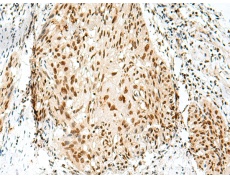

IHC positive control: |

Human esophagus cancer and Human tonsil |